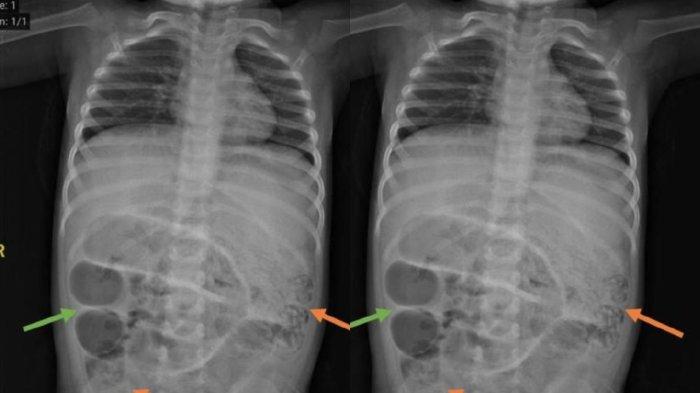

Seorang balita berusia 3 tahun tak BAB seminggu hingga perutnya membesar. Ternyata ususnya penuh cacing.

Setelah diperiksa dokter, penyebabnya adalah karena usus anak 3 tahun itu penuh cacing.

Pasalnya, ia sudah mengalami sakit perut, kesulitan bernapas, dan muntah.

Dokter di rumah sakit menduga hal tersebut terjadi karena ada sumbatan pada ususnya sehingga tidak berfungsi maksimal.

“Kemudian diperiksa CT scan, memang menggambarkan suatu kondisi yang disebut ileus obstruktif, yaitu buntunya saluran pencernaan akibat sesuatu,” ucap dia.

Setelah dioperasi, ternyata ada tiga titik sumbatan yang ditemukan oleh dokter dalam usus anak tersebut.